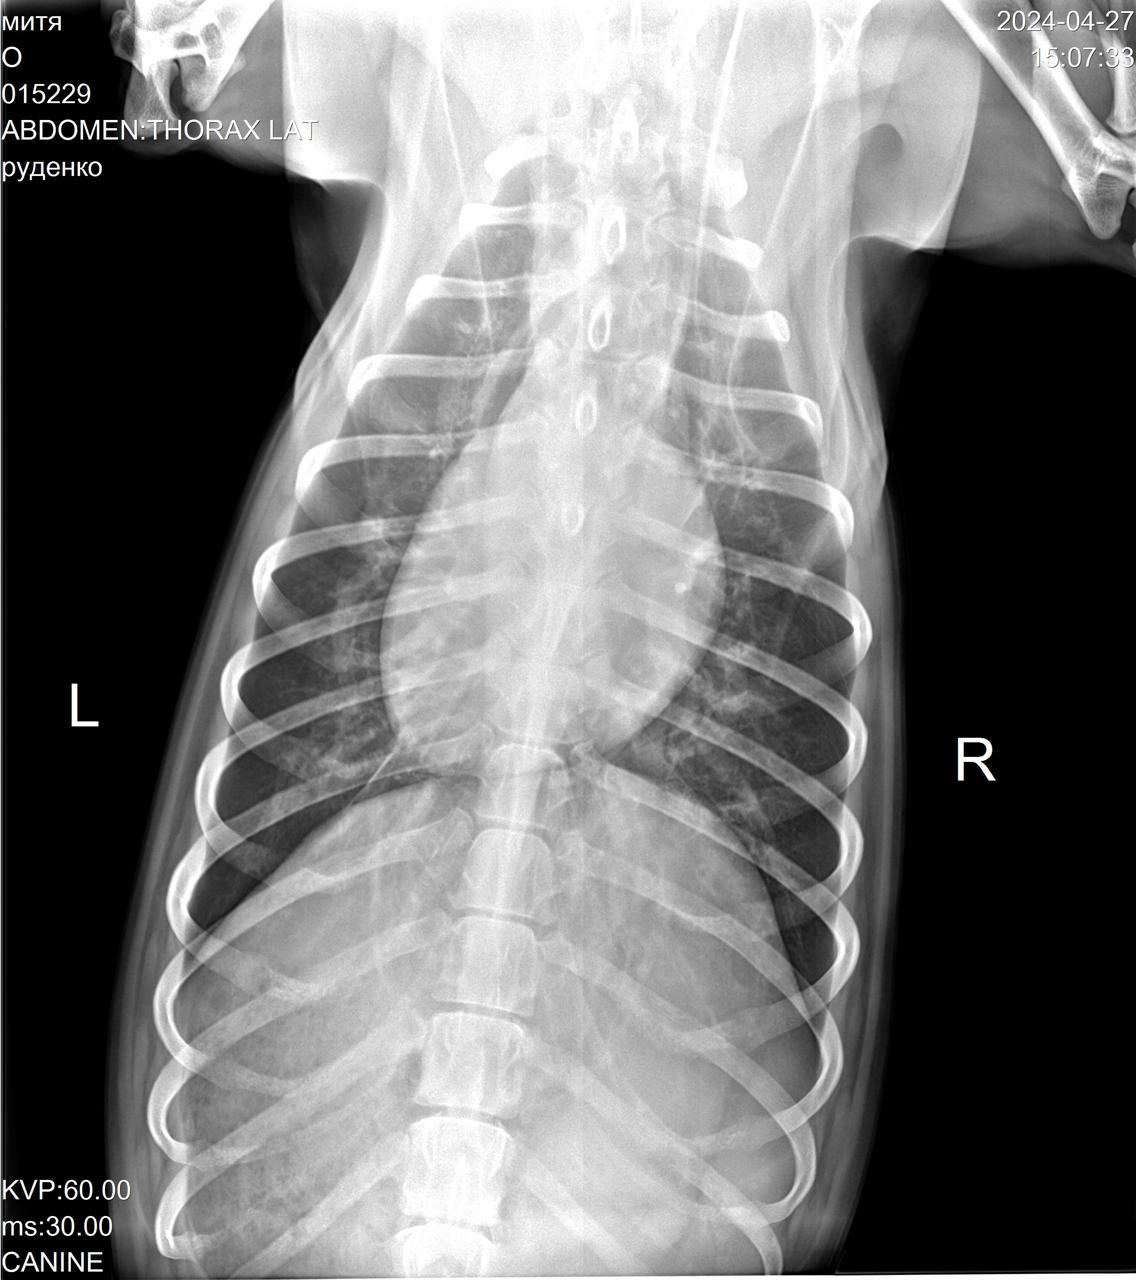

Сегодня Катюша возила Митю на рентген.

IMG-20240427-WA0028.jpg

IMG-20240427-WA0029.jpg

IMG-20240427-WA0030.jpg

IMG-20240427-WA0031.jpg

IMG-20240427-WA0032.jpg